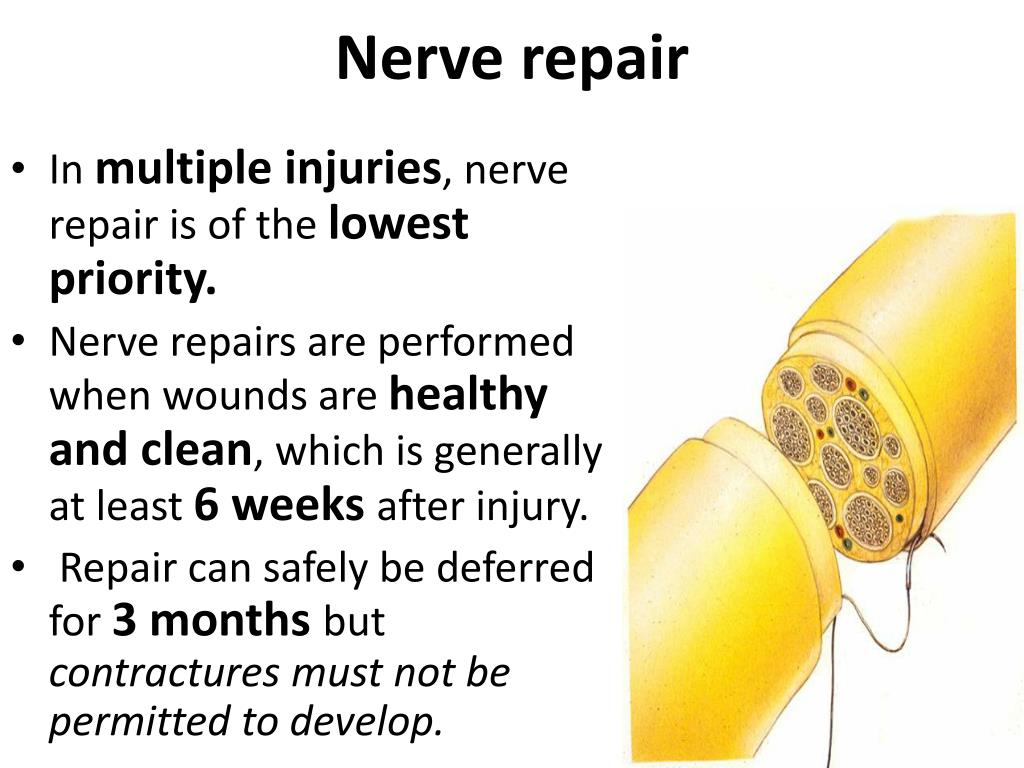

How to repair nerve damage. Clinically relevant anatomy nerve regrowth in the peripheral nervous system is dependent on the type of injury. Surgical intervention with nerve grafting is necessary to repair the injury. Surgical nerve repair involves exploration of the injured nerve and removal of injured tissue or scar from the nerve endings.

Surgery to repair brachial plexus nerves should generally occur within six months after the injury. How are nerve pain and nerve damage treated? Learn about the types, causes and benefits of nerve repair surgery, a treatment option for peripheral nerve injuries that restore function and sensation.

Surgeries that occur later than that have lower success rates. The nerves can grow back to their muscle or skin areas, but this process can take several months, and the messages between the. Functional disability due to nerve lesions is intertwined with the.